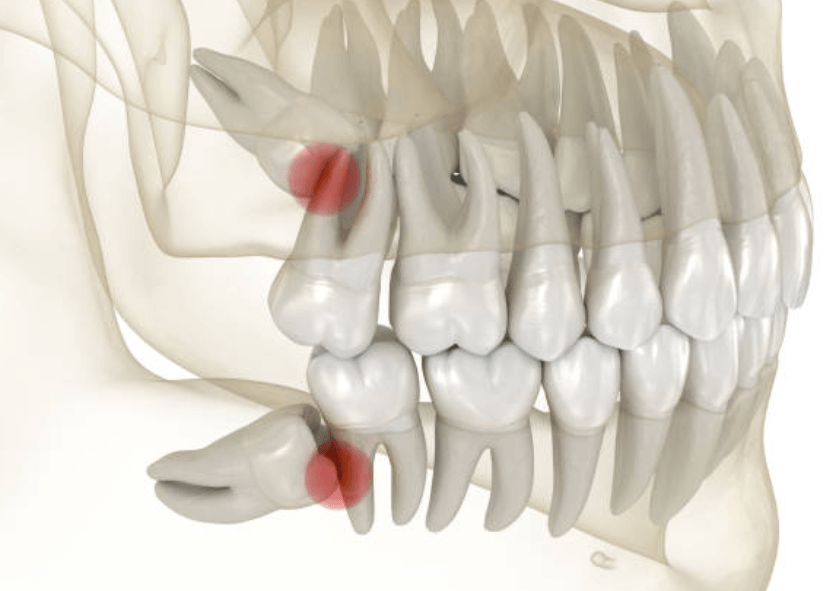

사랑니를 뽑으면 구멍이 생기는 것은 단순발치, 단순매복, 복잡 매복, 완전매복 등 케이스와 상관없이 무조건 생깁니다. 이빨을 뽑은 후에는 피가 채워지고 혈액 응고 작용으로 피가 굳어지는 과정을 거칩니다.

잇몸이 아무런 문제가 없다면, 잇몸과 뼈가 치유되는 과정을 거쳐 구멍이 메꿔집니다. 그러나 이 과정은 최소 1-2개월, 뼈가 완전히 회복되기 위해서는 3-6개월 이상의 시간이 소요됩니다.

드라이 소켓(Dry socket)은 응고된 피가 떨어지거나 완전히 아물지 않아 발생하는 상황입니다. 드라이 소켓이 생기는 원인은 아직 밝혀지지 않았지만, 일부 환자들은 노력해도 해결되지 않을 수 있습니다.

흡연, 침을 뱉거나 빨대를 사용하는 것, 악기 연주 등으로 상처 부위의 압력이 바뀔 수 있으며, 이미 드라이 소켓이 나타난 적이 있는 환자들은 드라이 소켓 가능성이 높습니다.